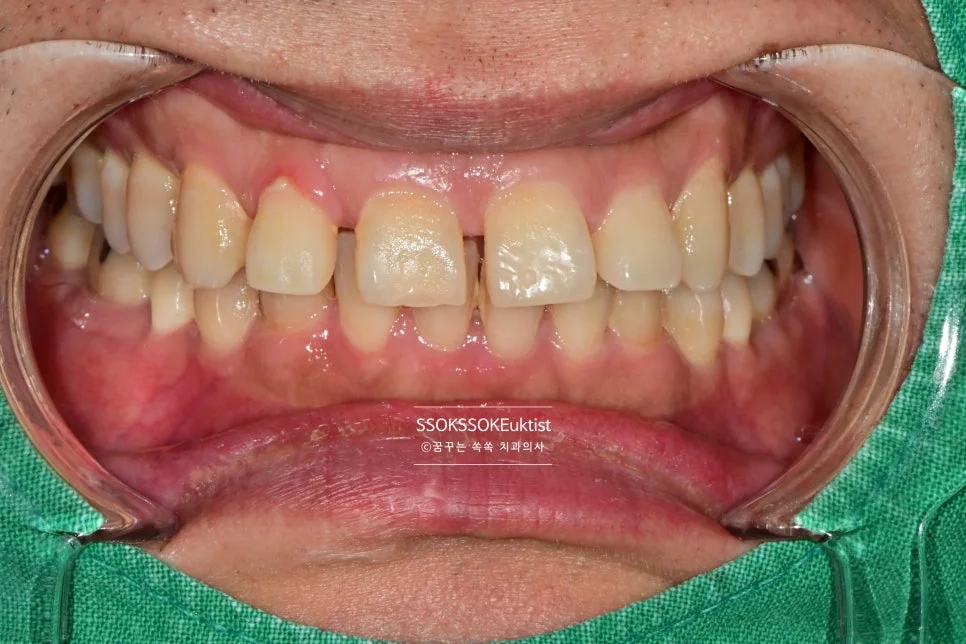

앞니 벌어짐 레진 치료, 교정 없이 하루 만에 해결할 수 있을까?

안녕하세요^^ 웃을 때 앞니 사이가 벌어져 보이면 은근히 신경 쓰이시죠? 사진 찍을 때 자신감이 떨어지고, 어떤 분들은 발음이 새기도 합니다.

이런 정중이개(앞니 사이 틈)는 많은 분들이 겪는 흔한 치아 고민 중 하나입니다. 그런데 이 벌어진 치아, 꼭 오래 걸리는 교정치료를 해야만 해결되는 걸까요?

측면에서 바라본 사진입니다. 생각보다 틈이 커서 한 치아만 치료할 경우 한 개 치아만 너무 커 보이는 게 될 것 같아, 양쪽 치아 모두 레진으로 치료하는 것이 좋습니다.